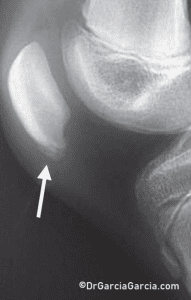

In children, jumper’s knee is equivalent to the “Sinding-Larsen-Johansson syndrome,” which causes similar symptoms and has similar treatment approaches. (fig 10)

Figure 10. X-ray of a child’s knee with pain at the inferior pole of the patella. This corresponds to an osteochondrosis due to Sinding-Larsen-Johansson disease.